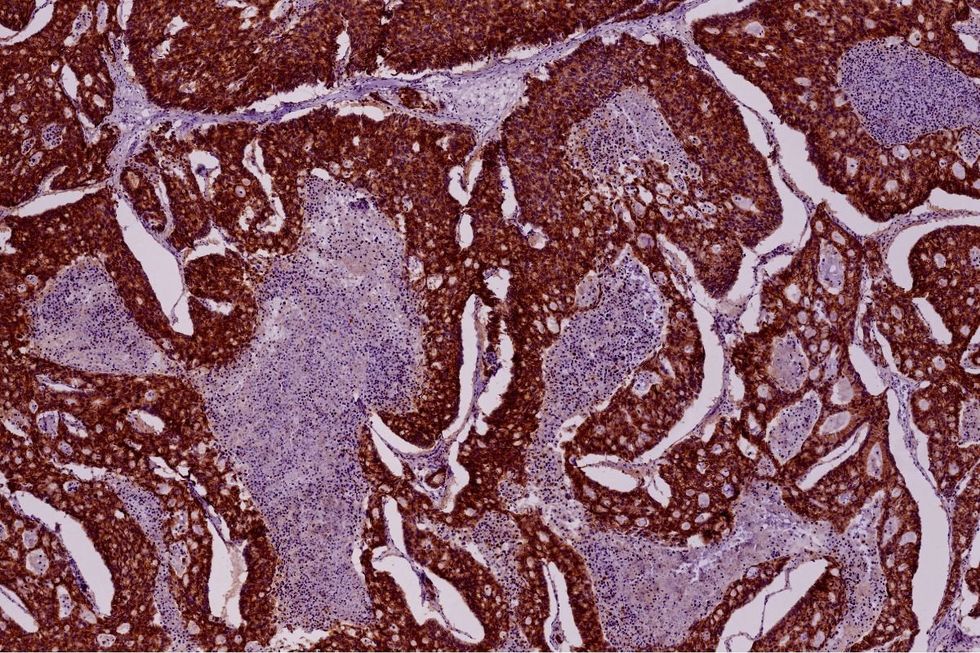

Doctor's discovered a tumour on Cori's pancreas (stock image)

Frustrated that her doctors couldn't find answers, she drove herself to the emergency room. A CT scan finally revealed the devastating truth - a tumour on her pancreas, lesions on her liver, and a mass on a nearby lymph node.